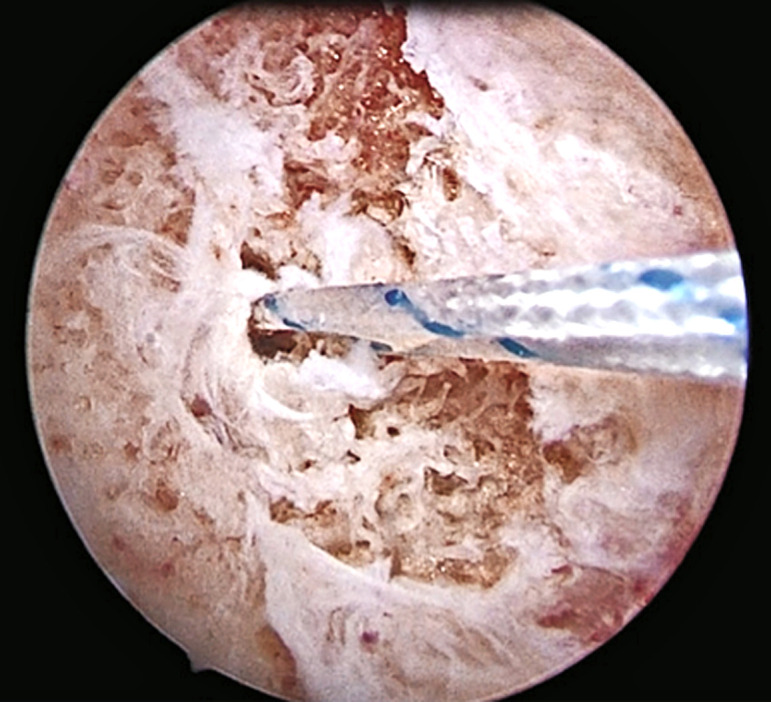

Abstract Image